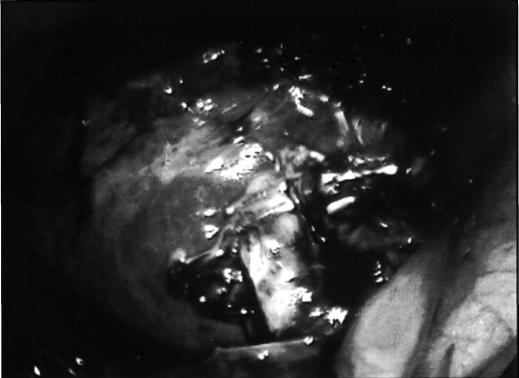

This is a report of a laparoscopic cholecystectomy in an 82-year-old white female with volvulus of the gallbladder presenting with a chief complaint of chest pain.

The patient had an uneventful recovery and was discharged within 72 hours after surgery, indicating that with the proper technique laparoscopic cholecystectomy is both feasible and safe in gallbladder volvulus.

这是一例82岁白人女性因胆囊扭转以胸痛为主诉接受腹腔镜胆囊切除术的报告。

患者恢复顺利,术后72小时内出院,表明采用适当技术,腹腔镜胆囊切除术在胆囊扭转中既可行又安全。